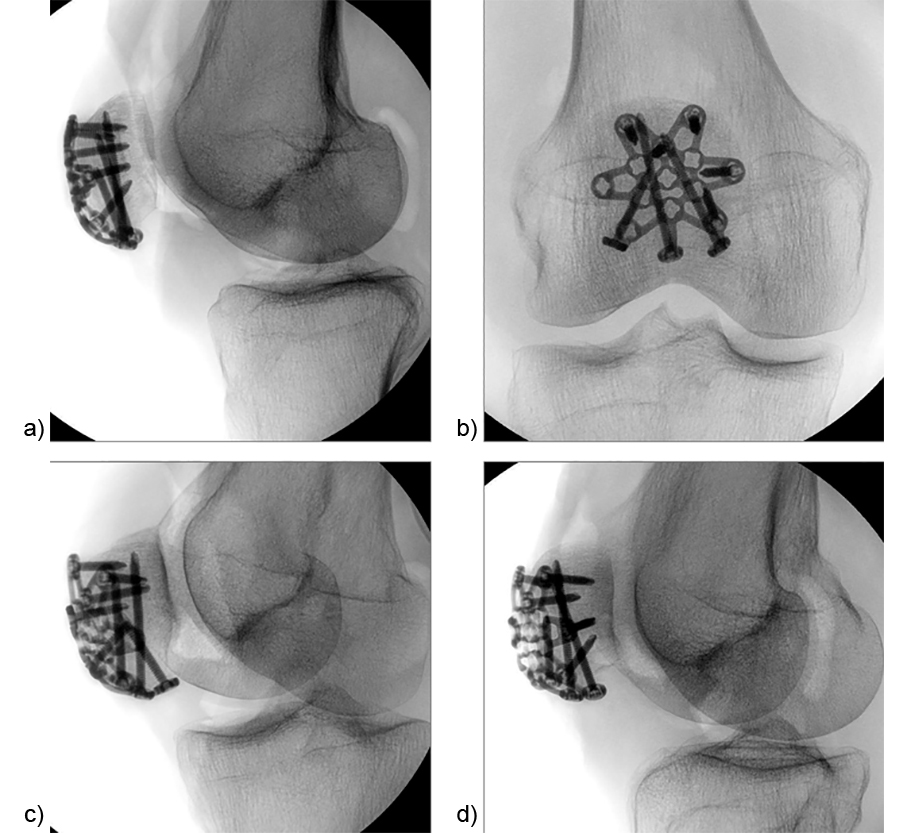

A 73-year-old woman sustained a right 34-C3.1 patella fracture during a hiking injury (Fig 1). X-ray analysis revealed that the distal pole was fractured in four fragments (Fig 2). After fracture reduction, a three-hole plate was used with three inferior to superior locking screws in the coronal plane through the holes of the plate legs and five anterior to posterior locking screws (Fig 3 and Fig 4).

After fracture reduction and temporary fixation, the plate template was used on the patella to select the appropriate plate size and to determine the best plate position with the desired location for the inferior to superior locking pole screw through the central plate leg (Fig 9).

A standard three-hole patella plate was chosen and bent according to the template. A central trans-patellar tendon stab incision was made to insert the middle plate leg when positioning the plate (Fig 10). The plate was provisionally fixed to the proximal patella fragment. The inferior to superior pole screw was inserted first as the 'primary' screw through the preselected plate hole of the middle plate leg to prevent collision with subsequent 'secondary' anteroposterior screws. Bicortical pole screw placement increases the stability of the construct. In this plate configuration the plate was used as a “basket plate” to stabilize the fracture. A second pole screw was inserted through the lateral plate leg.

The plate fixation was finalized by placing the monocortical AP locking screws. Subsequently, the sutures were tightened to the patellar tendon and the extensor mechanism (Fig 11). The plate may help to enhance the suture fixation.

Figure 12 illustrates the final fixation construct. The patient was allowed to perform early active knee movement at 2 weeks.